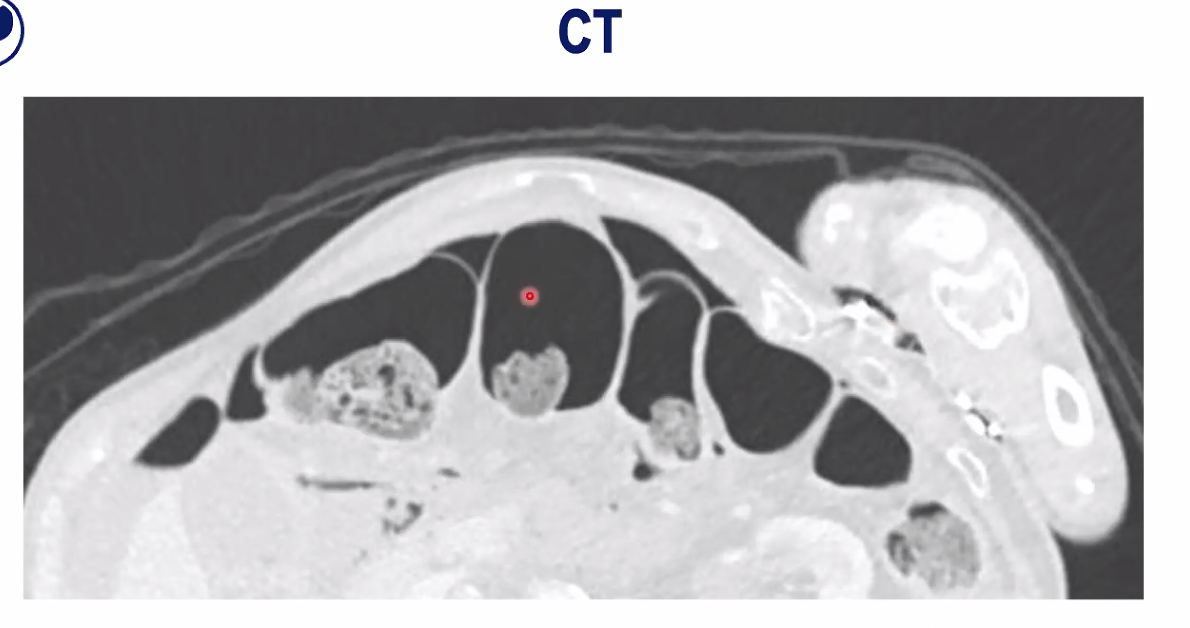

On right of image on left can see large bowel in black. Notice he has fluid around liver, which shouldnt be there. Can also see the pylorus, part of his stomach, coming down to his duodenum, and you’ll see there’s a defect here. So he’s had a pretty unusual duodenal perforation, and it’s been posterior.

The CT on the right has been adjusted so we can see where the air is.

Black is air inside large bowel and can see faeces inside it, and then can also see free air, that is outside the large bowel and that explains the Rigler’s sign. When got air on both sides, can see the walls very clearly.

Black is air. So can see slits of black which represent air in the abdomen near where the perforation is, so this gives you a clue where it is going on. So this is certainly a perforation and you can be pretty much 99% sure it’s coming from his duodenum.